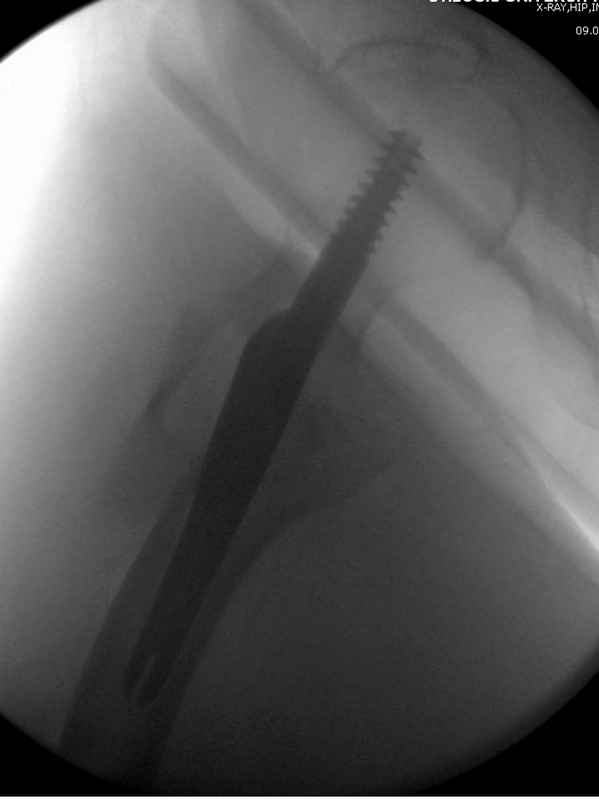

Здесь 83 года, травма в результате падения